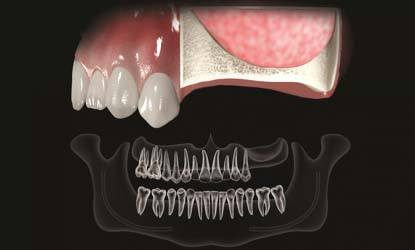

Problema: Nepakankamas kaulo aukštis dantų implantui

Tikslas:

Pakeisti trūkstamą dantį dantų implantu per vieną kartą

Rezultatas:

Atlikta sinuso elevacijos procedūra ir dėka gero pirminio stabilumo vienmomentiškai įsriegti dantų implantai